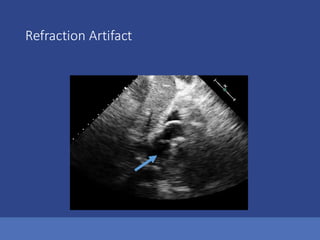

3.Refraction Artifacts

Refraction Artifact

Ultrasound Assumption Violations Anotherway to think about these Axial Direction Artifacts located below the real Structure Lateral Direction Artifacts located to the side of the real Structure 1.Reverberations 2.Mirror Image Artifacts 3.Acoustical shadowing or enhancement 1.Beam Width Artifacts 2.Side Lobe Artifacts 3.Refraction Artifacts